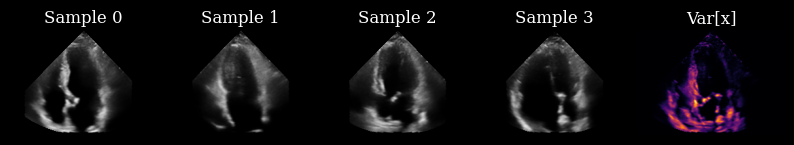

Initially, we have not yet acquired any measurements, so we draw samples from the prior to drive our actions.

prior_samples = model.sample(n_samples=n_prior_samples, n_steps=n_unconditional_steps, verbose=True)

scan_converted_prior_samples = scan_convert(

data=keras.ops.squeeze(prior_samples, axis=-1), **parameters

)["data"]

posterior_variance = ops.nan_to_num(ops.var(scan_converted_prior_samples, axis=0))

fig, _ = plot_image_grid(

list(scan_converted_prior_samples) + [translate(posterior_variance, range_to=(-1, 1))],

titles=[f"Sample {i}" for i in range(n_prior_samples)] + ["Var[x]"],

vmin=-1,

vmax=1,

cmap=["gray"] * n_prior_samples + ["inferno"],

)

90/90 ━━━━━━━━━━━━━━━━━━━━ 26s 102ms/step